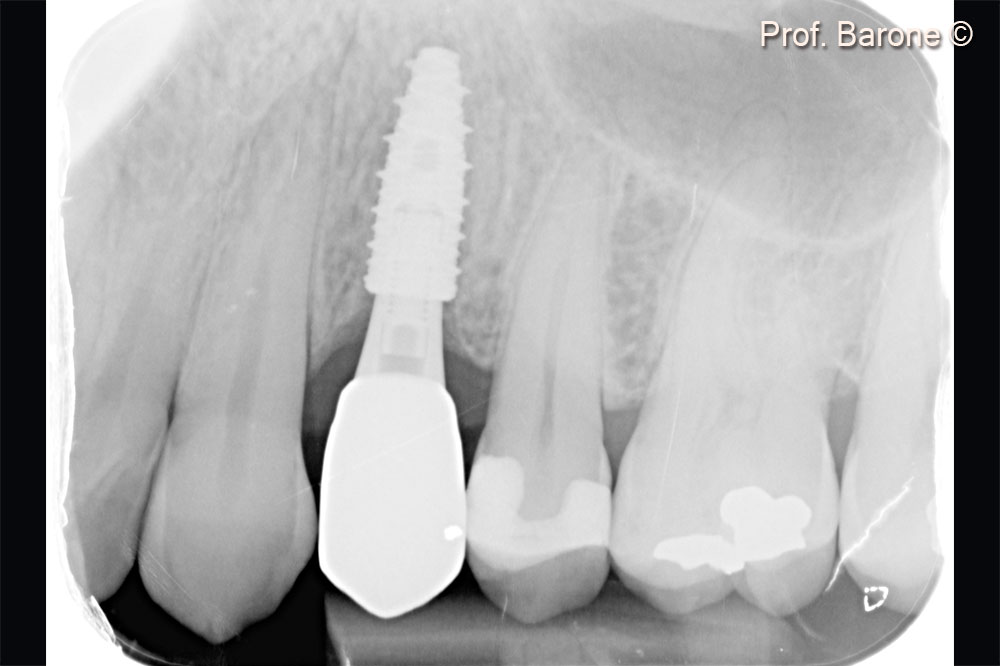

Periapical radiograph after implant placement